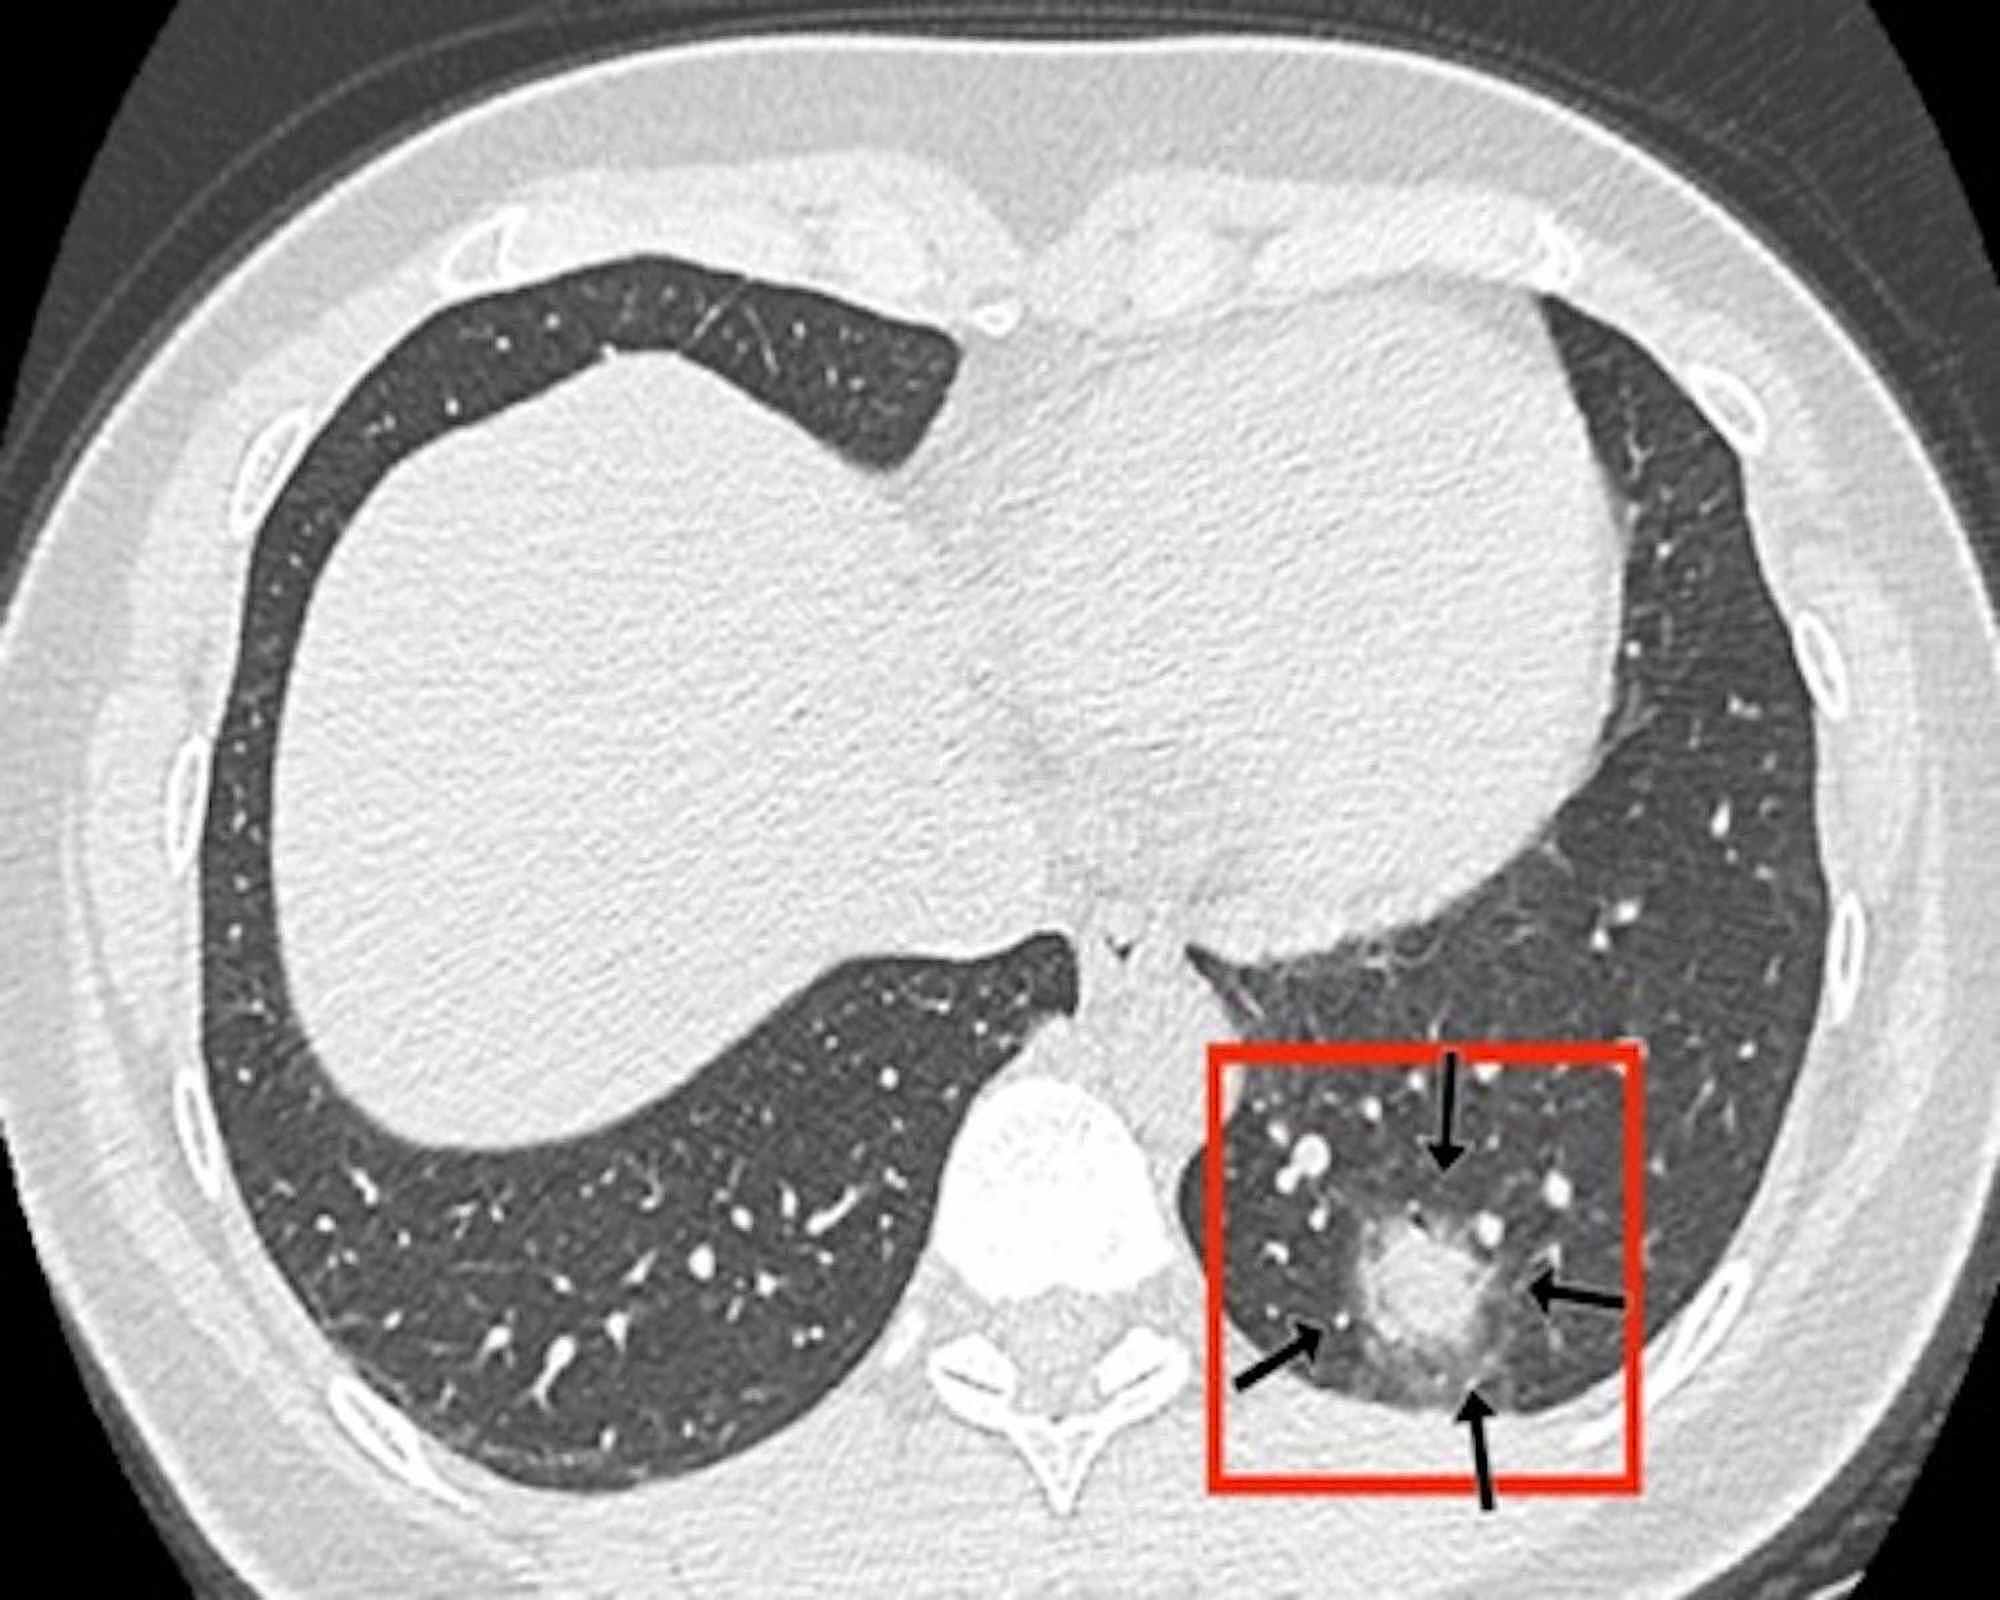

The distinctive CT features in our cohort are summarized in Table 3, including GGO and consolidative patchy mostly amorphous (72%) lesions, bilateral posterior and peripheral multi-lobar lung involvement, pleural effusions, subpleural fibrotic lines, subpleural sparing, vascular engorgement, occasional crazy paving, occasional mediastinal lymphadenopathy, pleural thickening, lack of cavitation, and absence of reverse halo (atoll) signs.

Subpleural sparing, which was observed in this patient cohort, has never been reported before, whereas mediastinal lymphadenopathy has been reported occasionally in the literature in English [11]. Focal vascular engorgement, septal thickening, and a subpleural fibrotic line were seen frequently in our cohort, with frequencies of 83%, 72%, and 61%, respectively.

Patients’ CT features are presented in detail in Figures 3, 4, 5, 6, 7, 8. A majority of cases (56%) had moderate severity scores. There was no correlation between the severity score and mortality, p=0.790 (Table 4).